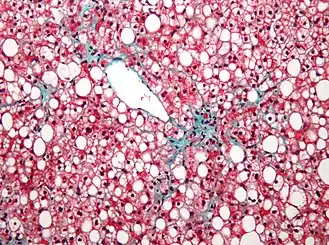

Микропрепарат ткани печени при неалкогольной жировой болезни печени: макровезикулярный стеатоз гепатоцитов. | |

Стеатоз печени (жировой гепатоз, жировая инфильтрация печени) — наиболее распространённый гепатоз, при котором в печёночных клетках происходит накопление жира. Накопление жира может быть реакцией печени на различные токсические воздействия, иногда этот процесс связан с некоторыми заболеваниями и патологическими состояниями организма.

Жировая инфильтрация печени, не связанная с действием алкоголя или других токсических веществ, называется первичным или неалкогольным стеатозом (неалкогольной жировой болезнью печени). Таким образом, далеко не всегда поражение печени связаны с действием токсических факторов (алкоголя, лекарственных препаратов).